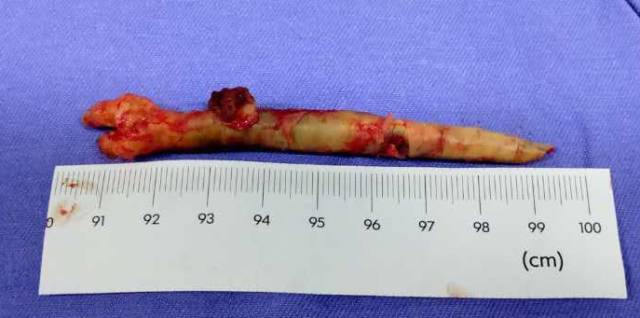

剥下的斑块:

手术过程:手术先切除颈总动脉动脉远端斑块,自远端颈内动脉处缝合至颈总动脉远端,夹闭颈总动脉远端,开放颈内动脉及颈外动脉,便于颈外动脉经颈内动脉向颅内代偿供血。再切除颈总动脉近端斑块,缝合后植入动脉鞘。视频如下。

此次分享两例颈动脉闭塞复合手术开通病例。第一例为颈内动脉长段闭塞,从颈内动脉起始段开始闭塞。患者术前存在眼动脉缺血事件及右侧半球灌注不足。颈内动脉剥脱后,颈内动脉可淡淡显影,为微导管通过创造条件。微导管通过后,顺利完成球囊扩张及支架植入,完全开通右侧颈内动脉。第二例为右侧颈总动脉闭塞患者,虽有颈外动脉代偿,但仍存在TIA及右侧大脑半球灌注不足。经颈动脉内膜剥脱后,造影可见颈总动脉显影,但管腔严重不规则,经球囊扩张及支架植入后,颈总动脉显影好。两例患者术后7天复查颈动脉CTA,均显示颈内动脉起始处较术后造影增粗。